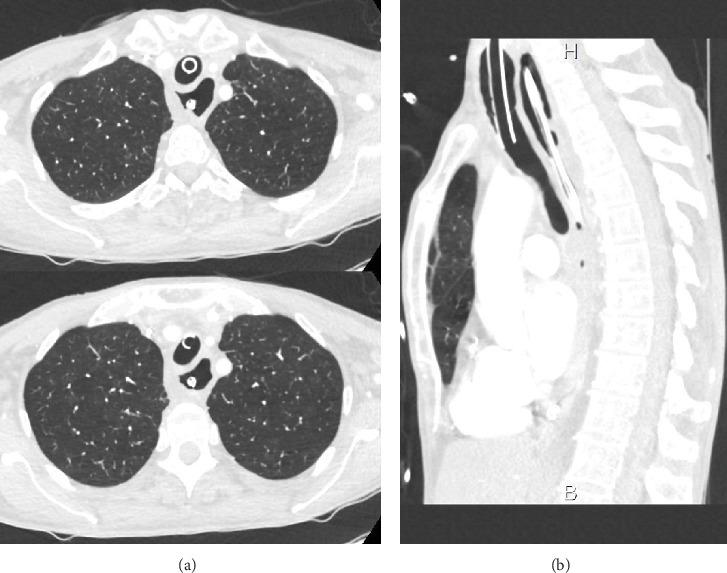

We report the case of an 80-year-old woman who presented one episode of cardiopulmonary arrest and two episodes of acute airway obstruction. We found in this patient the presence of tracheomalacia caused by megaesophagus compression secondary to achalasia probably responsible for episodes of acute airway obstruction and cardiopulmonary arrest.

我们报告了一名80岁女性的病例,该患者出现了一次心肺骤停和两次急性气道梗阻。我们发现该患者存在由贲门失弛缓症继发的巨食管压迫导致的气管软化,这可能是急性气道梗阻和心肺骤停发作的原因。